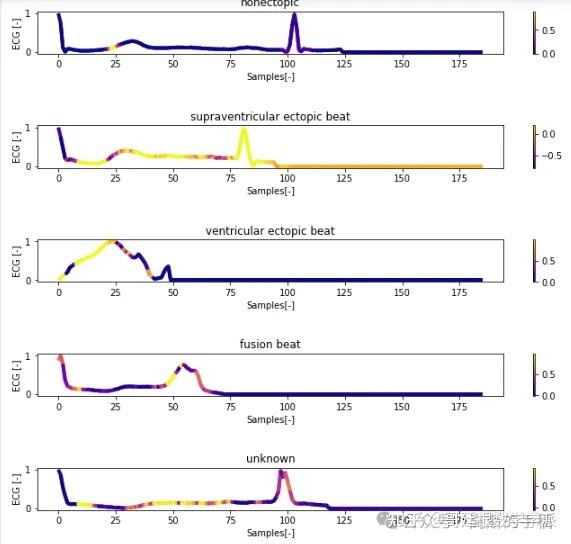

一维神经网络的特征可视化分析-以心电信号为例(Python,Jupyter Notebook)

包括Occlusion sensitivity方法,Saliency map方法,Grad-CAM方法